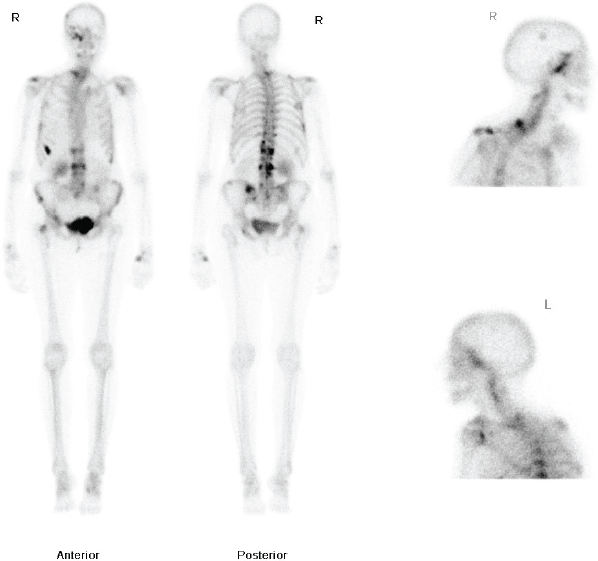

Figure 1: Whole body nuclear medicine bone scan showing increased uptake in the right ethmoid and maxillary sinuses.

The patient had a medical history of a T1cN1Mo oestrogen receptor-positive, right-sided ductal breast carcinoma, diagnosed in 1983. She was treated with a lumpectomy and radiotherapy. She subsequently developed a second left-breast T2NOMO ductal carcinoma in 1991, which was treated surgically by mastectomy. Following her mastectomy, she received adjuvant Tamoxifen for 10 years. In 2009, she developed pain in the thoracic area and a bone scan was requested. This demonstrated increased uptake in the dorsal-thoracic and lumbar spine, left hemipelvis, right femoral neck, ribs, right skullbase, and sphenoethmoidal recess (Figure 1). She was treated with radiotherapy to the lumbar spine (8 Gy single fraction) and started on letrozole due to the oestrogen receptor-positive status of the primary tumour. The patient was started on a course of IV pamidronate, along with monitoring bone scans, to reduce the risk of osteoporosis related to both letrozole therapy, and repeat dual energy X-ray absorptiometry (DEXA). Over the following two years, her repeat scans did not show progression of the disease process and she remained well on letrozole therapy, until she presented to her GP with the symptoms noted above.